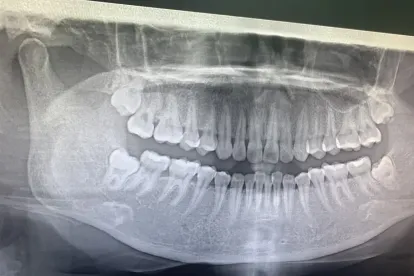

Most dental clinics in Thailand maintain international hygiene standards and use modern equipment such as digital X-rays, 3D scanning, and painless injection systems. Many dentists are trained abroad and communicate fluently in English, making the entire process smooth for international visitors. When it comes to tooth extraction — whether it’s a simple removal or a surgical procedure — Thai dentists are known for their gentle approach and focus on patient comfort.